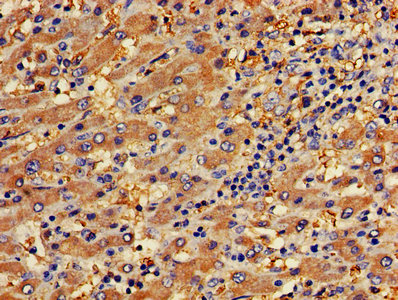

• IHC image of CSB-PA017767LA01HU diluted at 1:400 and staining in paraffin-embedded human liver cancer performed on a Leica BondTM system. After dewaxing and hydration, antigen retrieval was mediated by high pressure in a citrate buffer (pH 6.0). Section was blocked with 10% normal goat serum 30min at RT. Then primary antibody (1% BSA) was incubated at 4°C overnight. The primary is detected by a biotinylated secondary antibody and visualized using an HRP conjugated SP system.